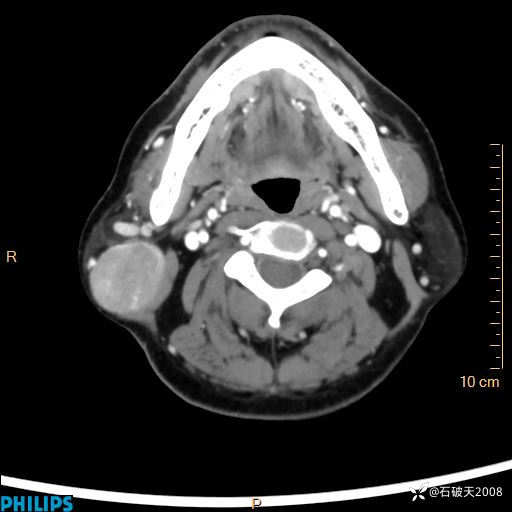

动脉期